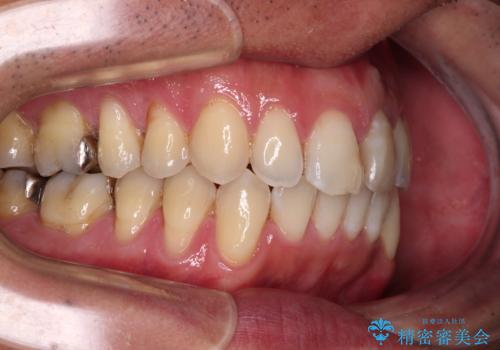

下顎にワイヤー装置を装着し、暫くしたところでやはりインビザラインにて矯正治療をしたいとのことで、インビザラインに切り替えました。

短い期間でしたがワイヤー装置を使用したことでデコボコが解消されたため、インビザラインの比較的短い期間で矯正治療を行うことができました。